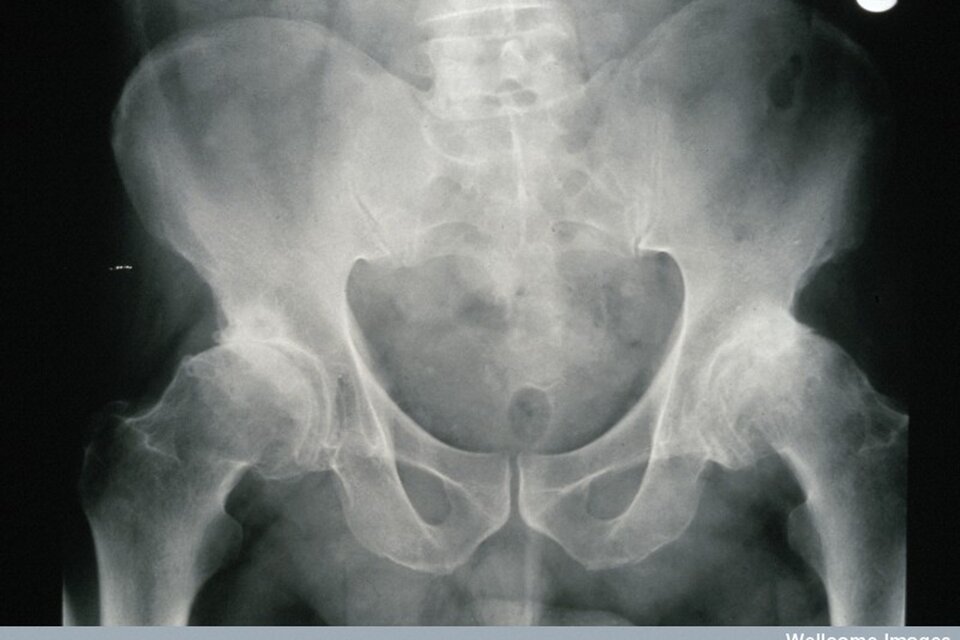

Badanie ultrasonograficzne (USG) wykonuje się, by ocenić stan wątroby, trzustki, śledziony, dróg żółciowych i pęcherzyka żółciowego. Uwidacznia ono na monitorze strukturę tych narządów oraz pozwala wykryć zmiany i nieprawidłowości, takie jak zrosty, guzy, kamienie, cysty. Badanie to pozwala także wykryć obecność płynu w jamie brzusznej. Aparat USG wykorzystuje fale akustyczne o wysokiej częstotliwości, nieinwazyjne dla człowieka.